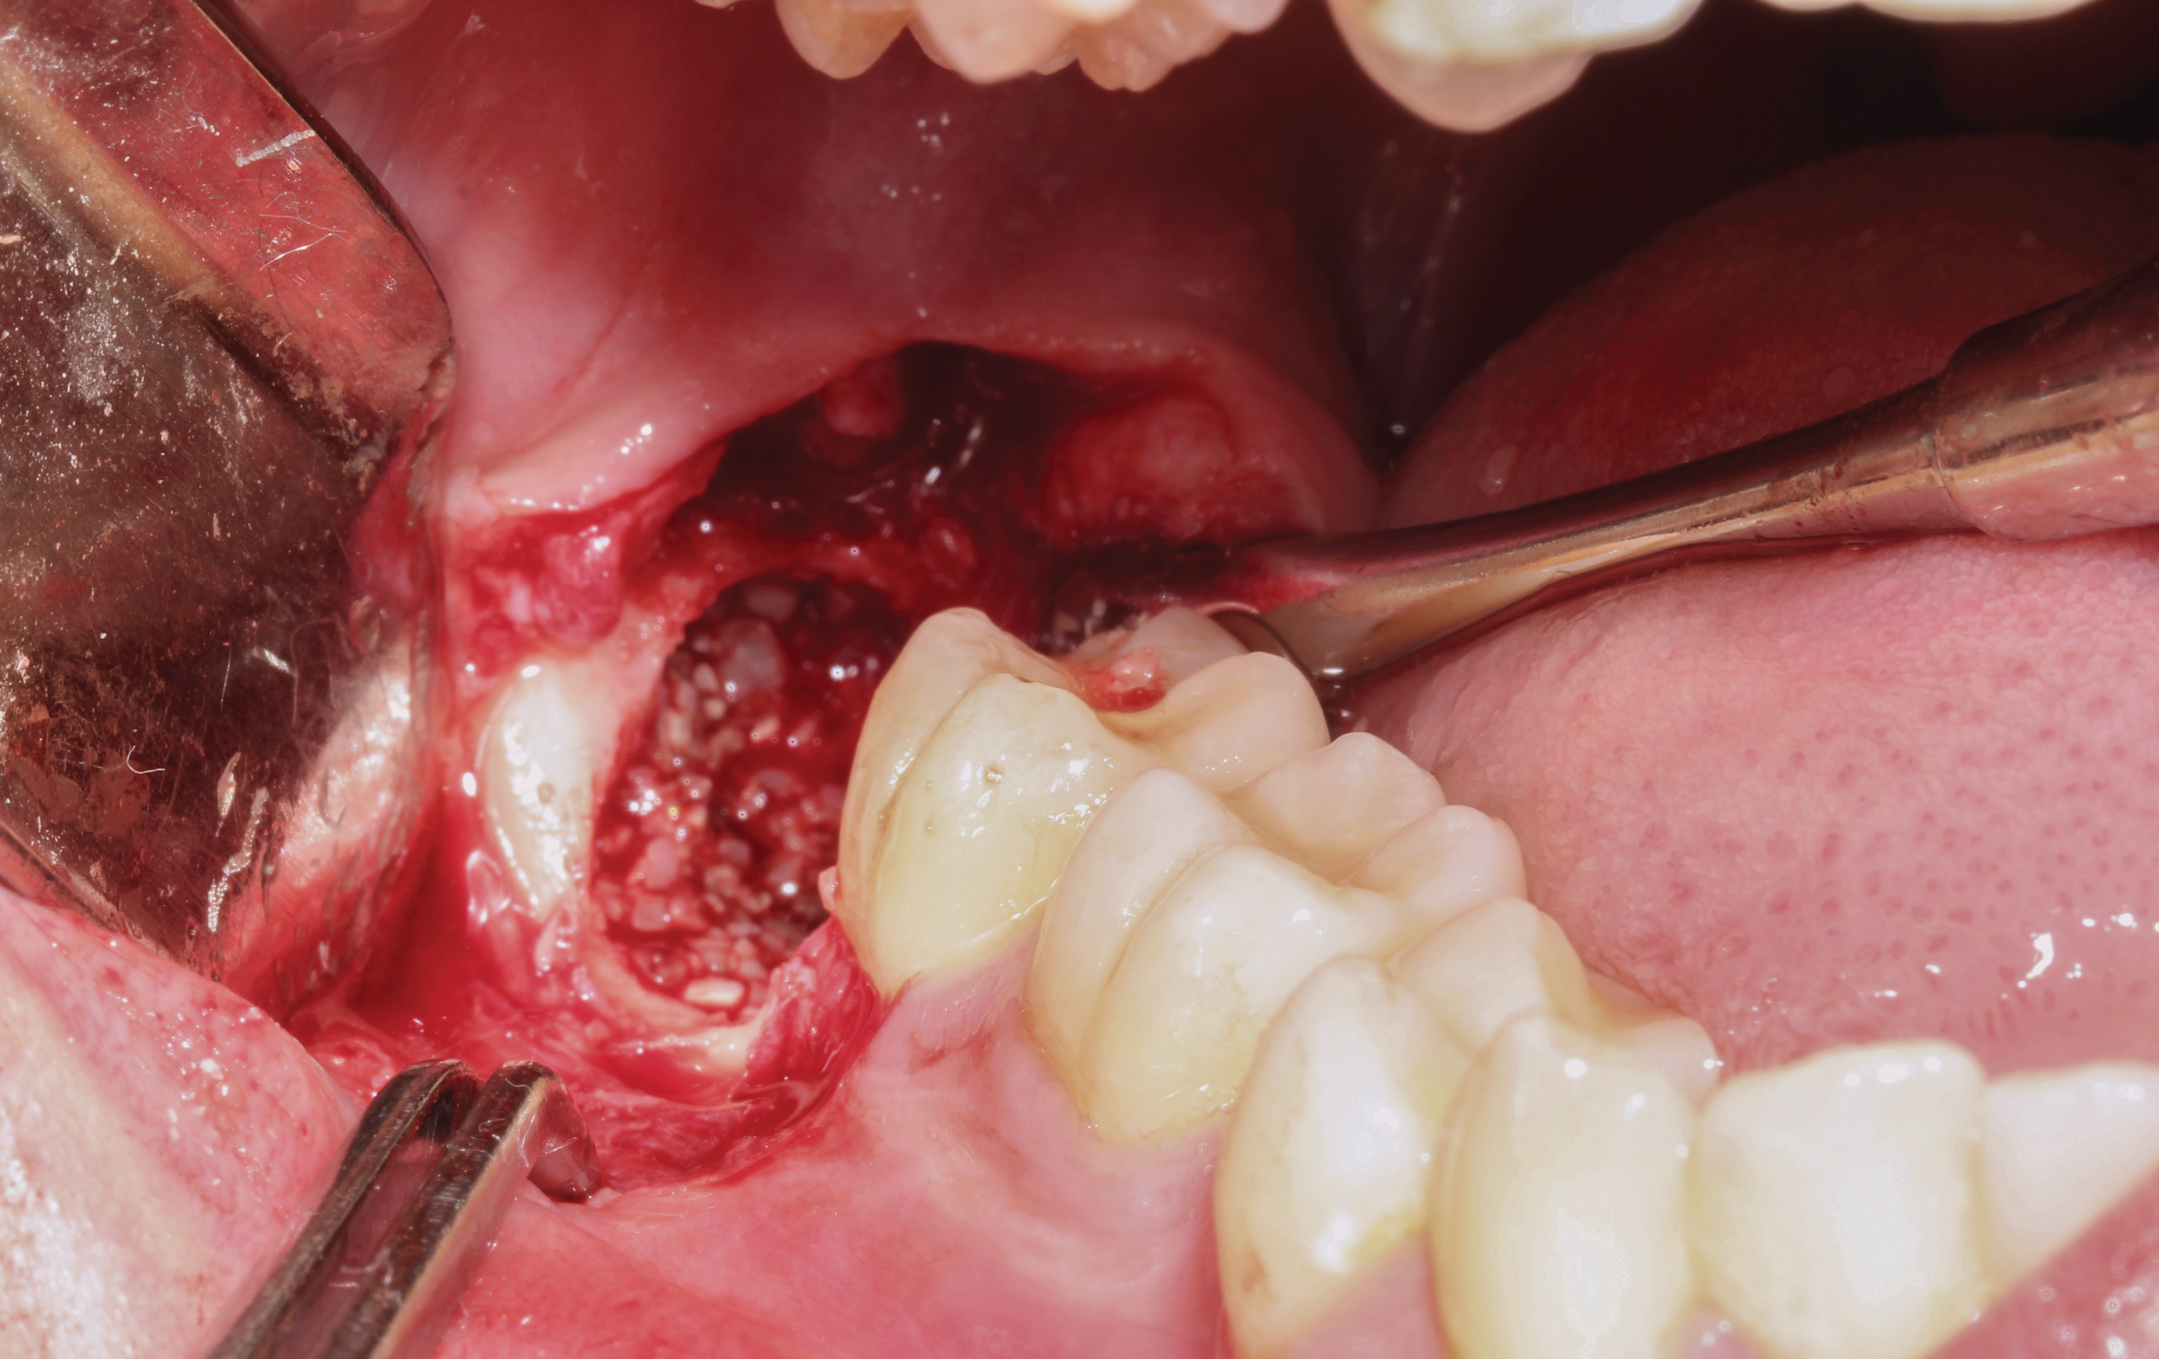

A presurgical rinse of 0.2% chlorhexidine (CHX) solution was performed, followed by administration of local anesthetic using 4% articaine with epinephrine solution. A crestal incision with a vertical releasing incision at the mesial aspect of the surgical area was made, and a full-thickness mucoperiosteal flap was elevated (Figure 1). A buccal and, if required, distal osteotomy was performed using a round carbide bur on a straight handpiece. When necessary the tooth was dissected to allow it to be elevated and extracted (Figure 2). When performing the third molar extraction care was taken to not damage the adjacent second molar tooth nor its supporting alveolar bone. The extraction socket was thoroughly debrided with hand instruments and rinsed with a 0.2% CHX solution to decrease bacteria in the socket (Figure 3).35

The extracted tooth fragments were cleaned to remove caries if present as well as periodontal ligament (PDL) remnants (Figure 4). The tooth was ground into particles using the dentin grinder machine. The particles were then saturated for 10 minutes in a dentin cleanser solution (sodium hydroxide solution mixed in 20% ethanol); this was followed by a phosphate buffered saline wash, resulting in a bacteria-free, autogenous graft material ready for implantation (Figure 5).

Fig 2. The tooth was sectioned to allow for extraction while enabling the surrounding bone of the socket to be maintained.

Figure 2

Fig 3. Extraction socket after removal of the impacted mandibular third molar.

Figure 3